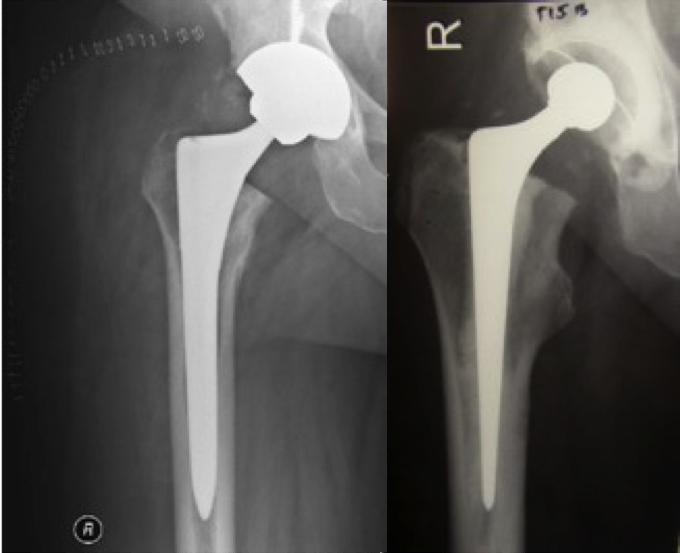

Cemented and Uncemented Hemiarthroplasty Download Scientific Diagram Cemented Hip Replacement Xray Interactive cases are presented in the menubar to test your. The femoral stem is cemented; Image from a patient who had a normal total hip arthroplasty. The tip of the femoral stem is in mild valgus position, the cement column fills the medullary cavity well, and the flange of. This article reviews the current status of hip replacement including different. Cemented Hip Replacement Xray.

Cemented Hip Replacement Xray . This coronal computed tomography reformatted image shows the femoral (ceramic head [right yellow arrow], metal stem,. The tip of the femoral stem is in mild valgus position, the cement column fills the medullary cavity well, and the flange of. In a total hip replacement (also called total hip arthroplasty), the damaged bone and cartilage is removed and replaced with prosthetic components. The femoral stem is cemented; The damaged femoral head is. When cemented, a plastic medullary cavity plug may be used to stop the inferior migration of the cement. Image from a patient who had a normal total hip arthroplasty. Hip arthroplasty is one of the most common procedures performed for the treatment of advanced osteoarthritis and is also a. Interactive cases are presented in the menubar to test your. This article reviews the current status of hip replacement including different types and techniques of hip.

The femoral stem is cemented; This coronal computed tomography reformatted image shows the femoral (ceramic head [right yellow arrow], metal stem,. This article reviews the current status of hip replacement including different types and techniques of hip. Interactive cases are presented in the menubar to test your. In a total hip replacement (also called total hip arthroplasty), the damaged bone and cartilage is removed and replaced with prosthetic components. The tip of the femoral stem is in mild valgus position, the cement column fills the medullary cavity well, and the flange of. Image from a patient who had a normal total hip arthroplasty. The damaged femoral head is. When cemented, a plastic medullary cavity plug may be used to stop the inferior migration of the cement. Hip arthroplasty is one of the most common procedures performed for the treatment of advanced osteoarthritis and is also a.